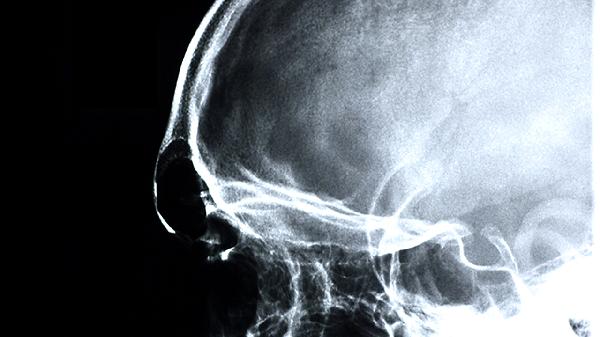

颅骨转移瘤可在头皮触及固定质硬的肿块,伴局部压痛或皮肤红肿。乳腺癌转移常形成溶骨性破坏,前列腺癌转移则以成骨性改变为主。X线或CT显示骨质破坏伴软组织影,必要时需活检鉴别原发灶。双膦酸盐类药物如唑来膦酸注射液可延缓骨破坏进展。